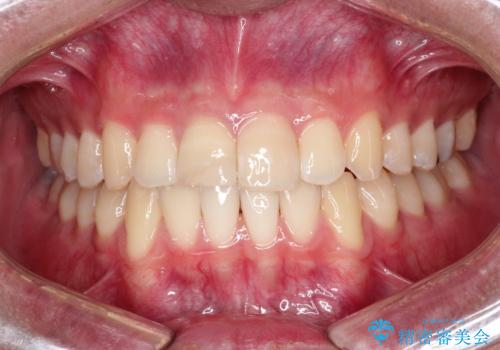

治療後、舌の可動域がかなり広がり患者様に大変ご満足していただけました。